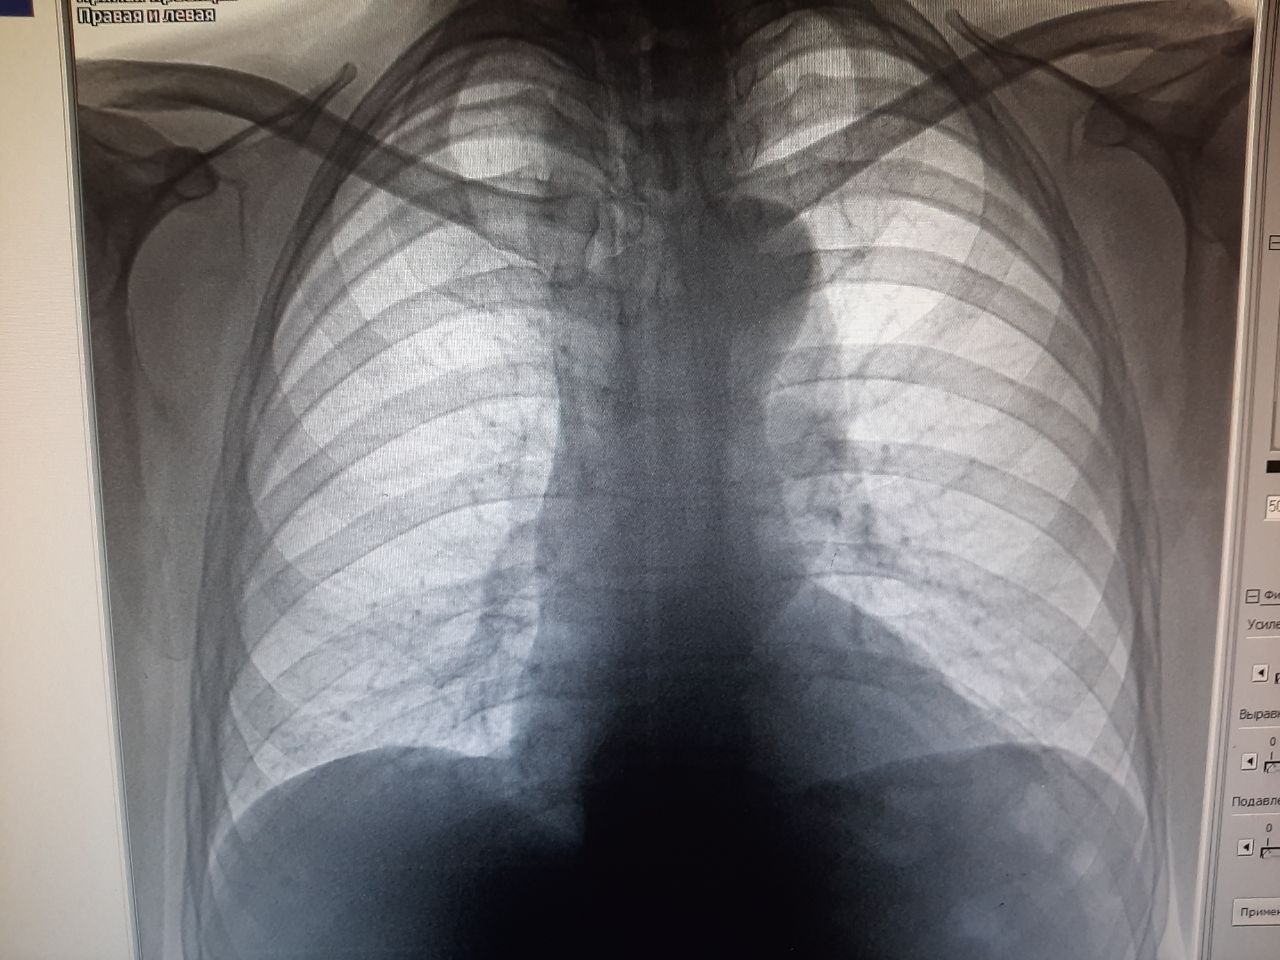

Роман in Radiology/Рентгенология Чатоид

Добрый день, подскажите, слева это может быть тень соска? снимок с небольшой ротацией, 60 лет пациенту, лежит с аппендицитом

мое мнение то что сосок здесь

Билол Халимов

Спасибо, рекомендовал КТ